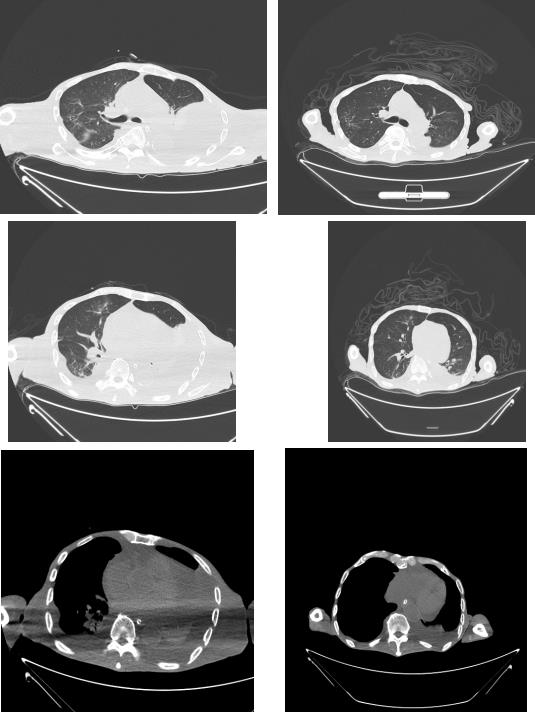

治療前胸部CT 治療后復(fù)查胸部CT

患者入院后檢查,發(fā)現(xiàn)肺部感染嚴(yán)重,合并胸腔積液、心包積液、中度貧血、嚴(yán)重低蛋白血癥、消化道出血、全身重度浮腫、多處褥瘡等情況,情況不容樂觀。更讓我們擔(dān)心的是,李大爺年事已高,身體的各個(gè)器官都出現(xiàn)了不同程度的損傷,如何在保證患者身體其他器官不受進(jìn)一步損傷的前提下,對患者的病癥進(jìn)行處理,是當(dāng)前急需解決的問題。